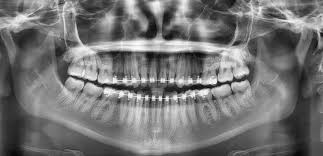

Radiología dental

Las radiografías son herramientas esenciales para el diagnóstico y tratamiento de enfermedades en el sector de la odontología. Esta tecnología ha evolucionado mucho, desde que en 1896 apareció la primera radiografía dental, captada por el dentista alemán Otto Walkhoff, hasta las imágenes digitales actuales.